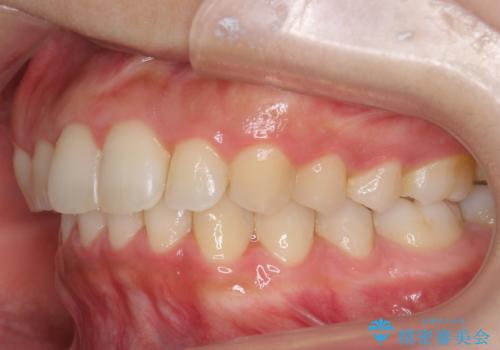

出っ歯の治療 抜かずに 短期間で目立たない治療

- 前歯のがたつきと突出を主訴に来院。

歯を抜かずに非抜歯で治療しました。

治療にも大変満足していただきました。

リファインメントも1回で済んでいます。